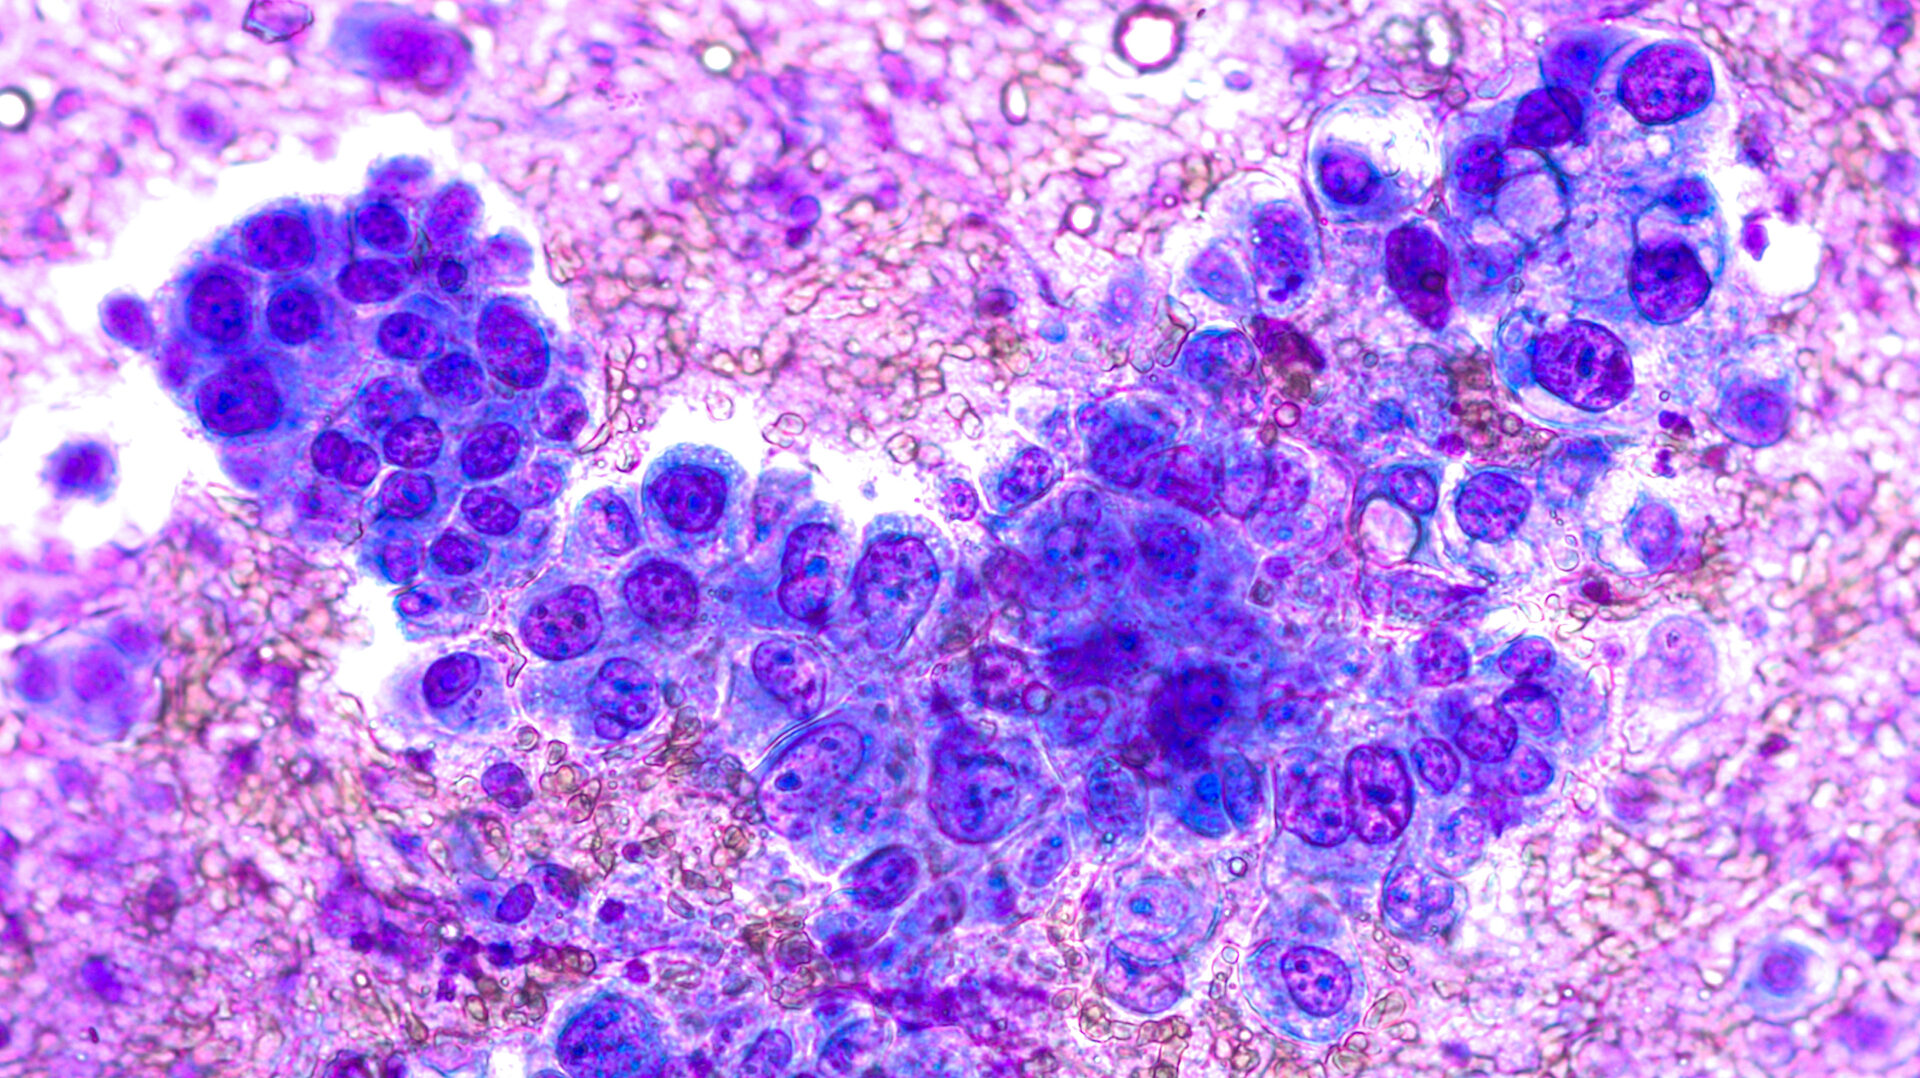

Photomicrograph of fine needle aspiration (FNA) cytology of a pulmonary (lung) nodule showing adenocarcinoma, a type of non small cell carcinoma (David A. Litman, Adobe Stock)